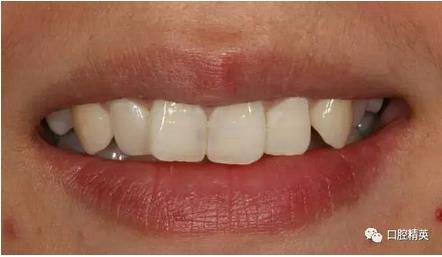

修復體戴入

口內(nèi)正側(cè)位及切端特寫

對比來看基本達到患者預期